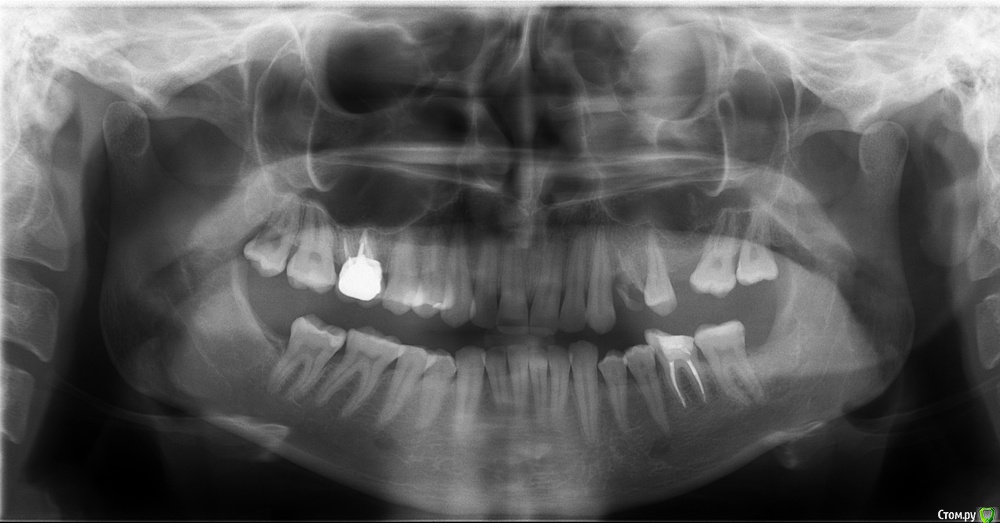

лягушка Опубликовано 11 декабря, 2015 Поделиться Опубликовано 11 декабря, 2015 Добрый день! Давно мучаюсь с проблемой зубов. Не могу принять решение - снесла мозг мужу и врачам. Хочу красивую улыбку. Проблемы -глубокий дистальный прикус, отсутствие 4ке и 6ке. 30 лет. Меня беспокоит отсутствие 4ке. Не сильно - отсутствие 6ке. Не правильный прикус не вызывает недовольство и комплексов. Многие говорят, что у меня красивая улыбка. Внешность полностью устраивает. Врачей волнует мой не правильный прикус. Итак, я уже слышала много мнений и очень разных. Как я поняла у меня три варианта. 1. Идеальный. Брекеты. Удаление 4ке. Операция. На этот вариант я не готова. Только если она жизненна необходима. 2. Компромисс. Удалять 4ку и возможно снизу еще два. Ставить брекеты. Далее имплантация на 8ку. Этот вариант меня смущает тем, что как я понимаю прикус мне он правильным не сделает да? зубы у меня будут ровнее. Но к ним у меня нет претензий. Я не могу понять лечение на брекетах будет лучше для здоровья моих зубов или просто поставит зубы в соответствии с нормами медицины. Так же по мнение врача ухудшиться внешний вид (так как зубы уйдут назад) возможно увеличение нижней губы. 3. Творческий))) Оставить свой прикус и в покое. Поставить имплант на 4ку. И чуть дорастить с помощью пломбы 5ку. Склоняюсь к нему. Но боюсь что будет дальше. Не будет ли это бомба замедленного действия- начнутся проблем с челюстью или зубами. Придется вырвать имплант и ставить таки брекеты. . Какие прогнозы на будущее?? Возможно ли дожить после брекетов со своими зубами до старости? Просто смысл их выравнивать если к годам к 50 придется менять на новые? Про лицо - если ставить брекеты это уменьшит или увеличит носогубную складку? Спасибо. Извините ))Всем лучик счастья) http://s018.radikal.ru/i524/1512/d0/4f17709addaat.jpghttp://s001.radikal.ru/i195/1512/a9/cc8180641ff4t.jpghttp://s020.radikal.ru/i721/1512/d9/75ef41300d90t.jpg http://s019.radikal.ru/i641/1512/c7/e1ff9243fe2ft.jpg http://s017.radikal.ru/i422/1512/dc/38aeb2319878t.jpg http://s017.radikal.ru/i407/1512/7f/2a9905741d88t.jpg Ссылка на комментарий